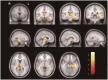

Results: In SPM8-based analyses, MTLE patients showed significant GMV reductions in the hippocampus ipsilateral to the epileptic focus, bilateral thalamus, and contralateral putamen in LMTLE patients. The GMV reductions were more extensive in the ipsilateral hippocampus, thalamus, caudate, putamen, uncus, insula, inferior temporal gyrus, middle occipital gyrus, cerebellum, and paracentral lobule in RMTLE patients. These patients also exhibited notable reductions of GMV in the contralateral hippocampus, thalamus, caudate, putamen, and inferior frontal gyrus. We observed that GMV reduction was positively correlated with several clinical features (epilepsy duration and seizure frequency in RMTLE, and history of febrile seizure in LMTLE) and negatively correlated with seizure onset age in both the RMTLE and LMTLE groups.